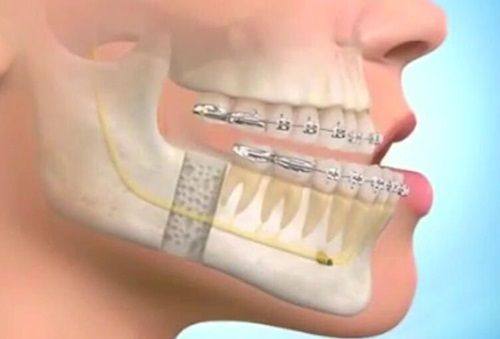

在擅长技术方面,韩相百医生专注于突嘴矫正手术。他针对骨骼导致的颌面异常情况,有着精细的判断和有效的治疗方案。当患者出现看起来嘴巴特别凸,牙齿垂直向下且牙列整齐的情况时,韩相百医生能够通过突嘴手术将前段凸出的双颌纠正到正常位置,术后再进行正畸收缝,达到理想的治疗成效。

1. 突嘴矫正手术:这是韩相百医生的招牌项目。对于骨骼导致的颌面异常,即嘴巴看起来特别凸,牙齿垂直向下且牙列整齐的情况,韩相百医生有着独特的治疗方法。他会精良行详细的检查和评估,然后通过突嘴手术将前段凸出的双颌纠正到正常位置。术后,患者需要进行正畸收缝,以达到更好的治疗成效。这种手术能够有效改善患者的面部外观,提升患者的自信心。

3. 牙齿正畸辅助:在突嘴矫正等手术中,牙齿正畸是重要的辅助环节。韩相百医生会根据患者的手术情况和牙齿状况,制定合理的正畸方案。他会选择合适的正畸器具,如牙套等,帮助患者调整牙齿的排列,使牙齿更加整齐美观。同时,他会密切关注正畸过程中的成效和变化,及时调整治疗方案,确保正畸成效达到至佳。